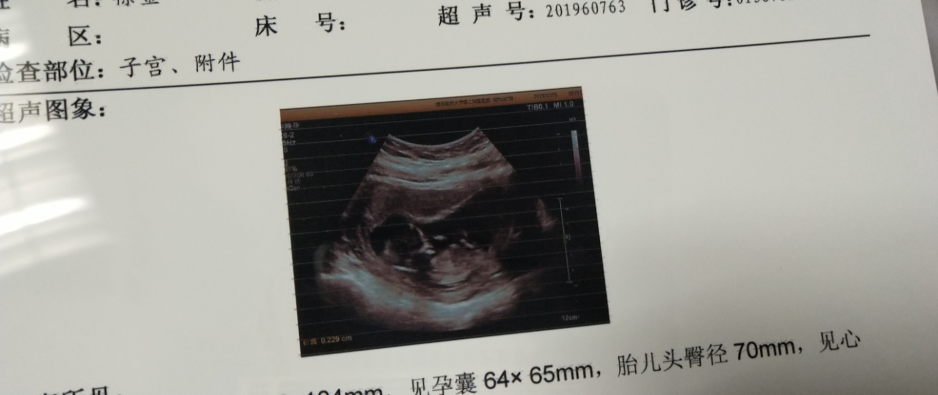

7月1日抽血有血值244.7,太好了,马上把好消息分享给了小姐妹们,过了一天查翻倍也是正常的。25日做B超可见胎心胎芽,今天NT也做了,这次是真的放心了。谢谢贝贝壳的小姐姐们一直在线上关心我的情况,不厌其烦地解答我各种问题,传好孕。

4天之后做了尿检和抽血,尿检显示阳性+,也是害怕,直到血值结果出来3462才确定是怀孕了,主任说血值还不错让隔天去看翻倍,我就隔了一天去查翻倍了,我当时就怕翻倍翻不好,还好,血值翻倍12329主任说不错,翻上去了,心里那个高兴啊,又让14天一超,这个时候我已经开始孕吐了,不过还好,没有吐的很厉害,前两天做了B超,宝宝一切正常,再过几周就要从生殖中心毕业了,希望后面一切顺利,祈祷。

今天做的B超,成功看见胎心胎芽。